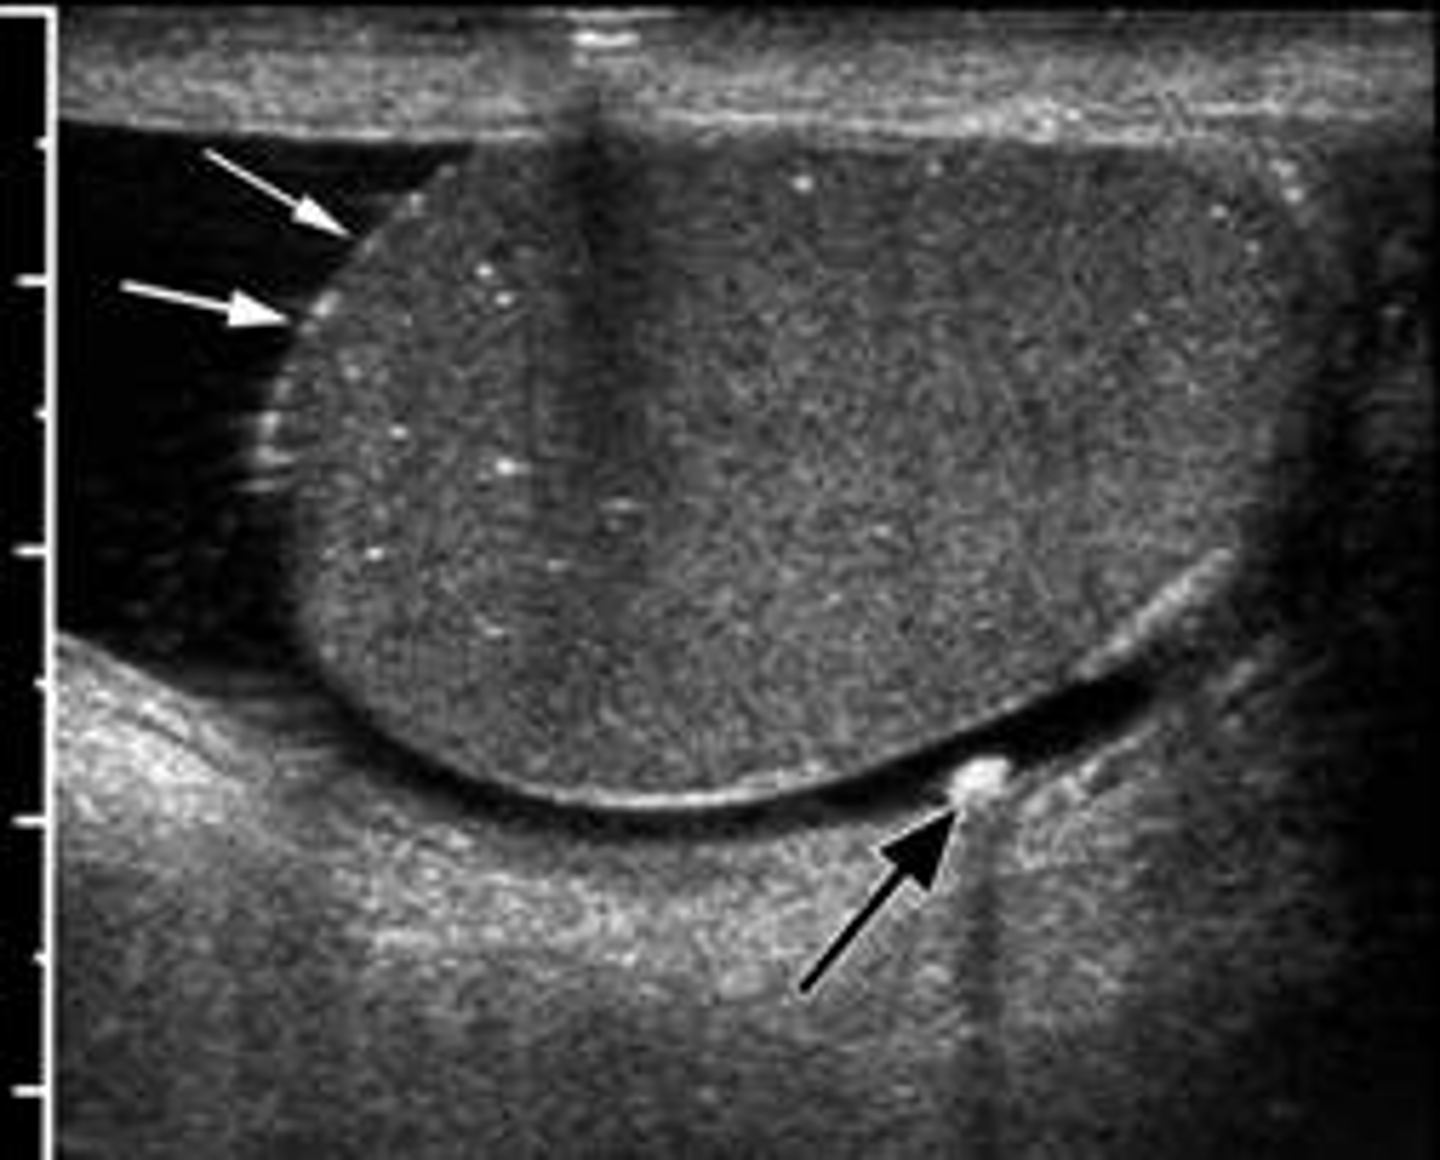

Multiple echogenic foci within the testis that produce no acoustic shadowing are termed:

a. Scrotoliths

b. Testicular microlithiasis

c. Teratoma

d. Epididymal cyst

Which of the following conditions has been associated with malignancy, infertility, Klinefelter syndrome, and cryptorchidism?

a. Hydrocele

b. Varicocele

c. Testicular microlithiasis